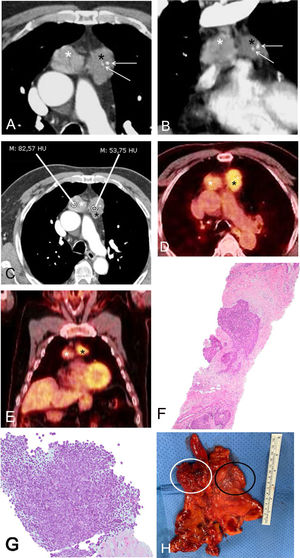

A) y B) Imágenes axial (A) y coronal (B) de TC de tórax en las que observan dos masas en mediastino anterior: una masa derecha (asterisco blanco) y una masa izquierda (asterisco negro). Nótese la presencia de focos de calcificación en la masa izquierda (flechas). C) Imagen axial de TC de tórax en la que se aprecia claramente la diferente atenuación de las masas mediastínicas: la masa derecha (asterisco blanco) presenta una atenuación media de 83 unidades Hounsfield mientras que la masa izquierda (asterisco negro) presenta una atenuación media de 54 unidades Hounsfield, sugiriendo un origen independiente. D) y E) Imágenes axial (D) y coronal (E) de PET/TC en las que se aprecia la diferente actividad metabólica de las dos masas mediastínicas (mayor avidez por la FDG por parte de la masa izquierda [6,1, asterisco negro] que por parte de la masa derecha [3,6, asterisco blanco]), sugiriendo dos tumores independientes. F) Muestra obtenida mediante biopsia percutánea de la masa mediastínica izquierda en la que observa una proliferación neoplásica de células epiteliales rodeadas de un tejido fibroso y sin apenas linfocitos, en relación con un timoma B3 (hematoxilina y eosina). G) Muestra obtenida mediante biopsia percutánea de la masa mediastínica derecha en la que se identifica un componente linfocitario mayoritario con algunos nidos de células epiteliales prominentes, en relación con un timoma B2. H) Pieza macroscópica postquirúrgica en la que se observan las dos masas contiguas (el círculo blanco corresponde a la masa derecha mientras que el círculo negro corresponde a la masa izquierda).

FDG: fluorodesoxiglucosa; PET/TC: tomografía por emisión de positrones; TC: tomografía computarizada.

Se trata de un varón de 75 años que llegó a consulta por una infección respiratoria y al cual se le detectó una alteración del contorno mediastínico en una radiografía de tórax. Una tomografía computarizada (TC) de tórax confirmó la existencia de dos masas sólidas en el mediastino anterior con características radiológicas diferentes, sugiriéndose dos timomas sincrónicos (fig. 1A, B y C). El paciente no presentaba síntomas que se consideraran una miastenia gravis. Una tomografía por emisión de positrones (PET)/TC demostró que cada masa mediastínica presentaba una actividad metabólica diferente (la masa derecha mostraba un SUV [valor de captación estandarizado] de 3,6 mientras que la izquierda tenía un SUV de 6,1), reforzando la idea de que se trataba de dos lesiones independientes (fig. 1D y E). Se decidió realizar una biopsia con aguja gruesa paraesternal, con control radiológico, de las dos masas mediastínicas, confirmándose que correspondían a dos timomas (uno derecho B2 y uno izquierdo B3, según la clasificación de la Organización Mundial de la Salud [OMS]) (fig. 1F y G). El paciente fue exitosamente intervenido quirúrgicamente (videotoracoscopia), confirmándose que se trataba de dos timomas sincrónicos estadios I de la clasificación TNM (pT1N0) y estadios IIB de la valoración de Masaoka (fig. 1H).